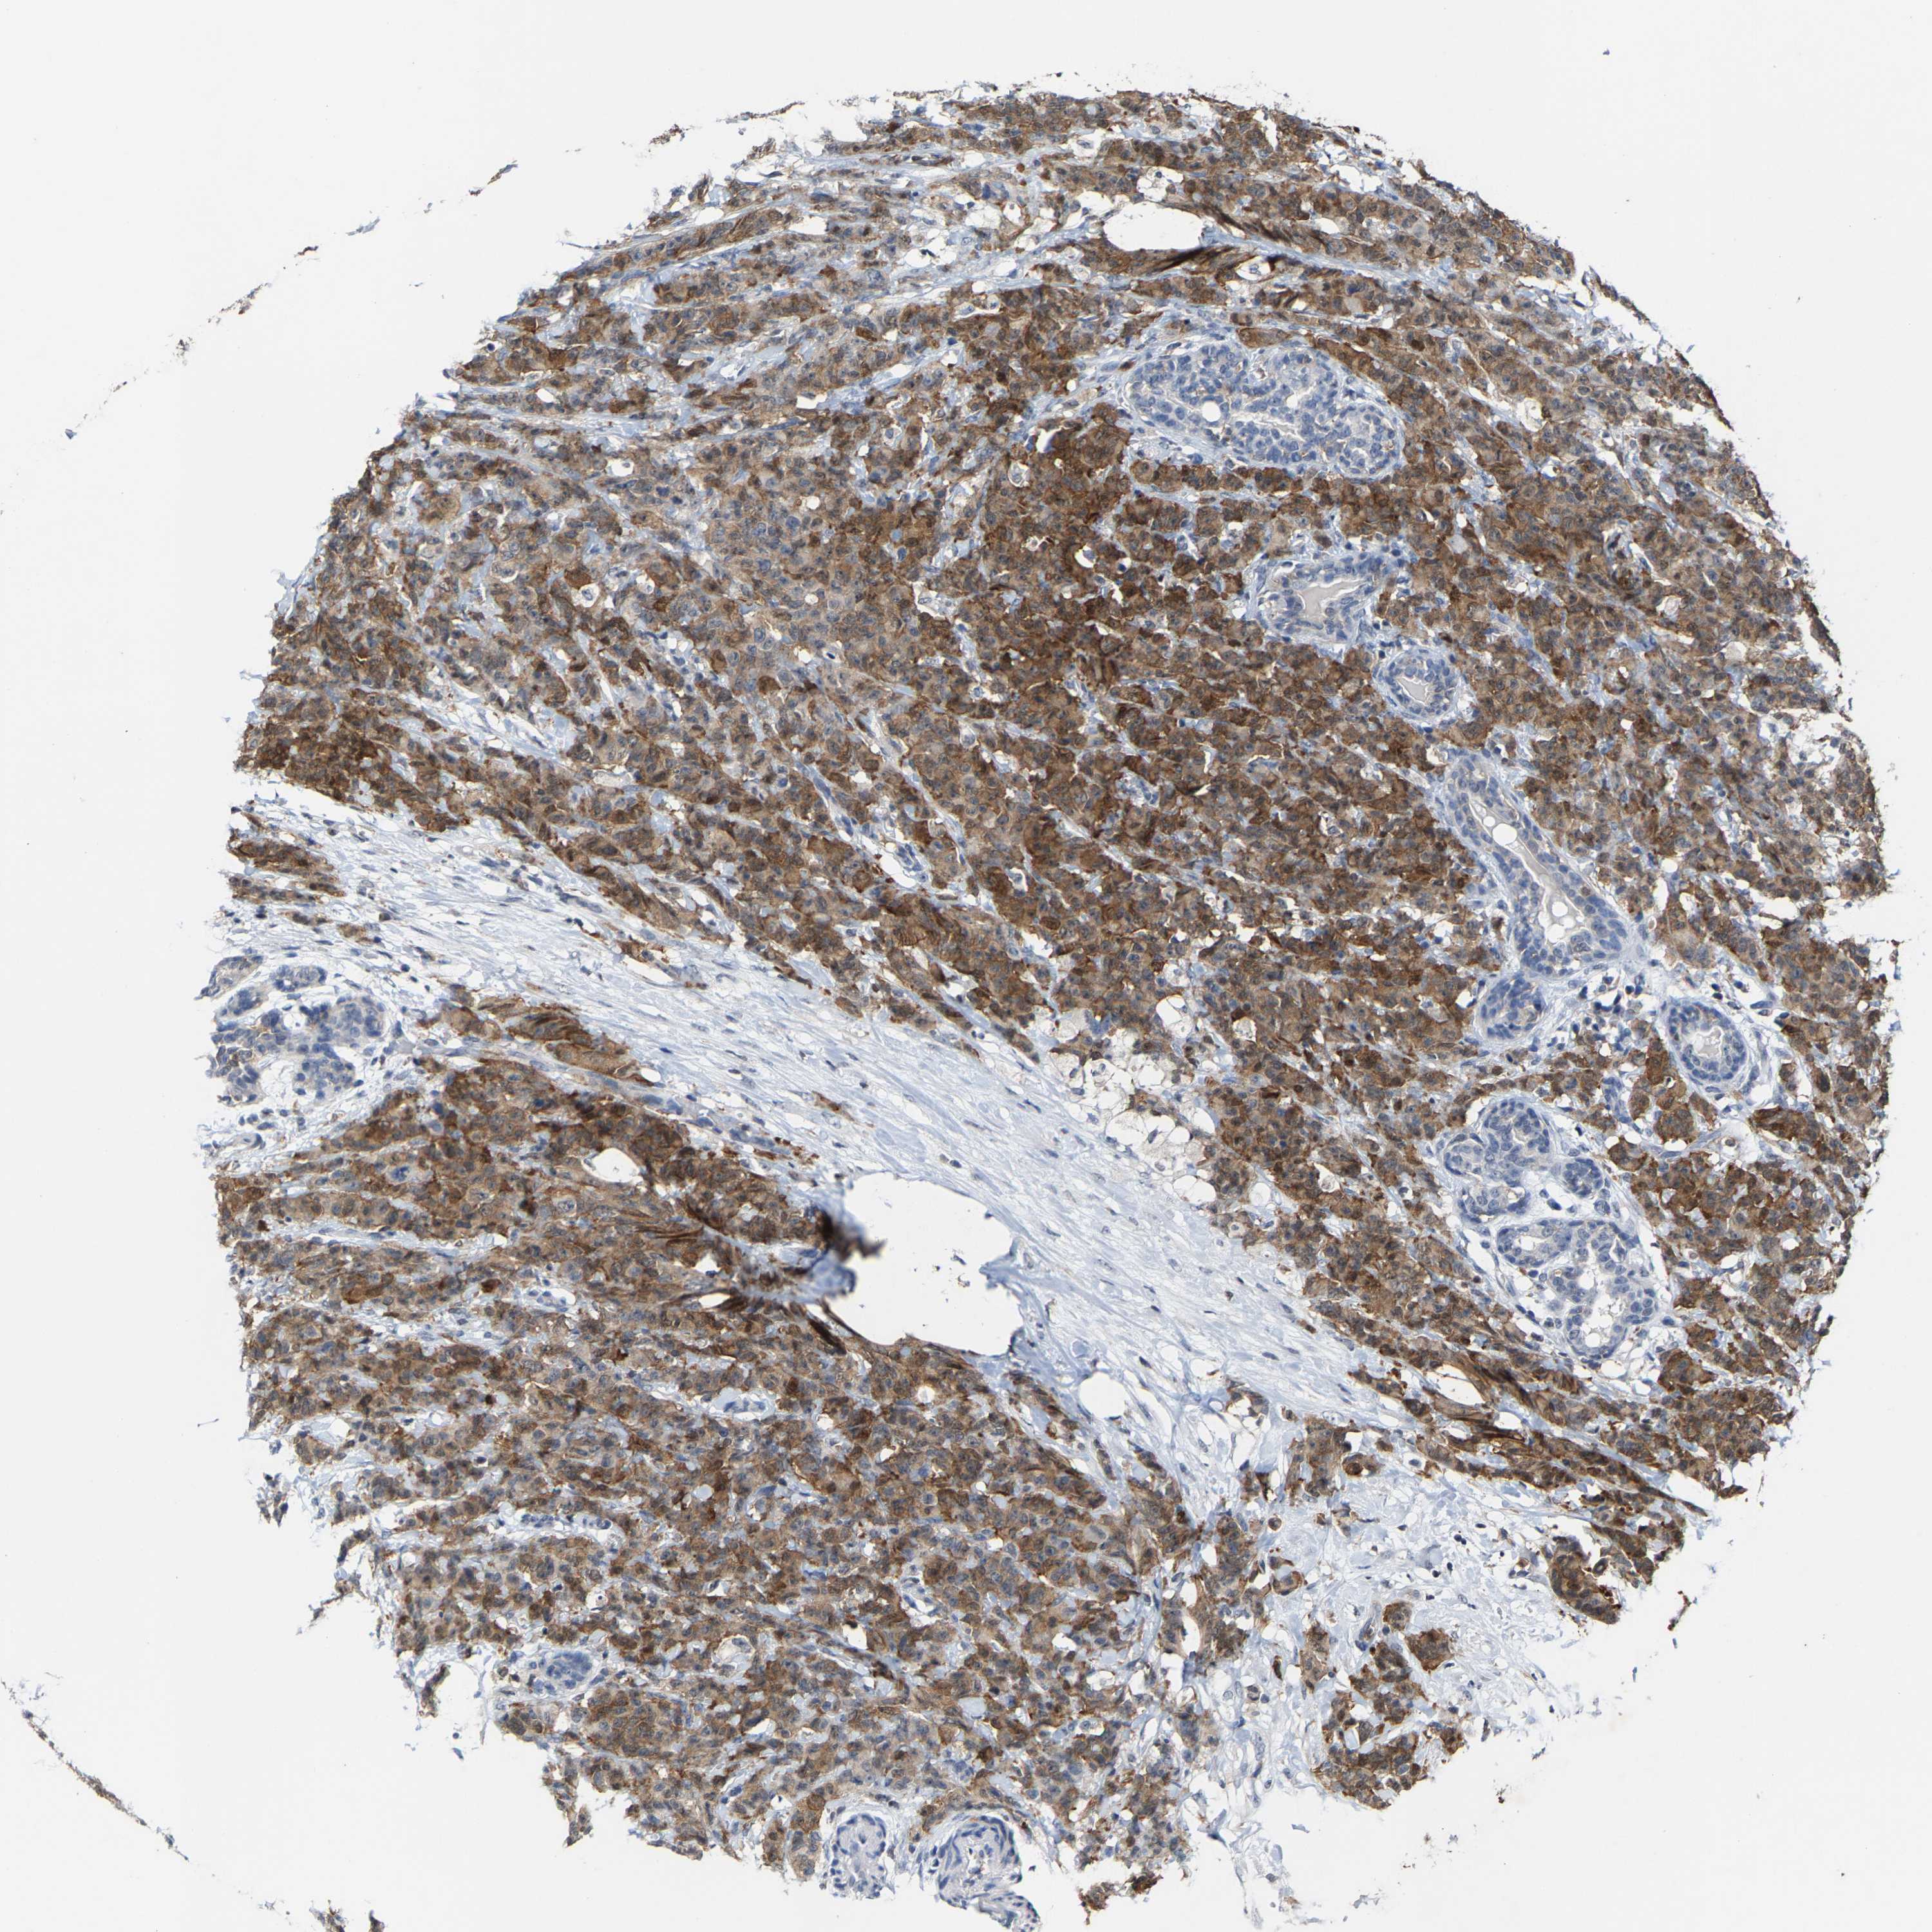

CANCER BREAST CANCER Show tissue menu

BRCA TCGA BRCA VALIDATION PROTEIN EXPRESSION